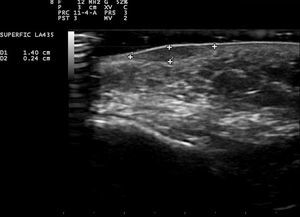

La ecografía cutánea (sonda 18MHz) del nódulo de la mejilla izquierda mostró una lesión dérmica de 1,37×0,24cm de tamaño, hipoecoica, bien delimitada, sin refuerzo posterior. No presentaba señal doppler ni depósitos de calcio en su interior (fig. 2).

La ecografía cutánea puede ser una herramienta útil para confirmar el diagnóstico de GAFI. El patrón ecográfico habitual es el de una lesión dérmica, sólida, hipoecoica, de límites netos y sin depósitos de calcio1. Solo en 2casos se observó una lesión hiperecoica con centro hipoecoico, una de ellas con refuerzo posterior5,7. El estudio en modo doppler fue negativo excepto en 2casos7,8. En nuestro caso, la ausencia de señal doppler puede estar en relación con el hecho de que la exploración ecográfica se llevó a cabo en una fase evolucionada de la lesión. Por tanto, la exploración doppler del GAFI puede depender del estadio evolutivo en el que esta se realice.